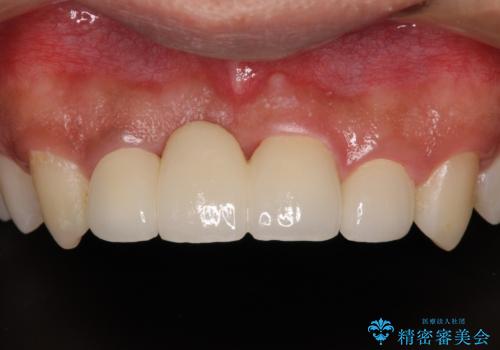

転んでぶつけて抜歯 前歯のオールセラミックブリッジ

抜歯後の欠損部はブリッジにて補綴治療を行うこととしました。

事故直後のレントゲン写真では全ての歯の根尖部に骨透過像が認められましたが、治療後には全ての透過像がなくなっていました。

診断に2-3ヶ月かかりましたが、的確に診断を行うことができました。